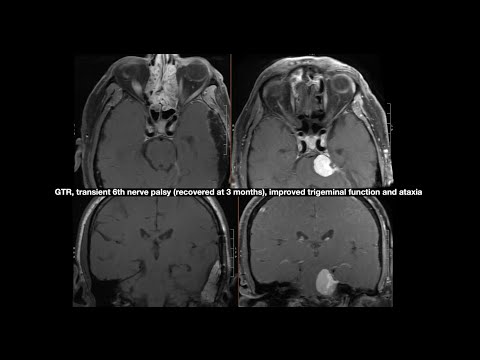

Hellow guys, Welcome to my website, and you are watching Transpetrosal Approach: Indications and a Video Review of Cases (Preview). and this vIdeo is uploaded by Neurosurgical Atlas by Aaron Cohen-Gadol, MD at 2013-07-31T19:28:59-07:00. We are pramote this video only for entertainment and educational perpose only. So, I hop you like our website.